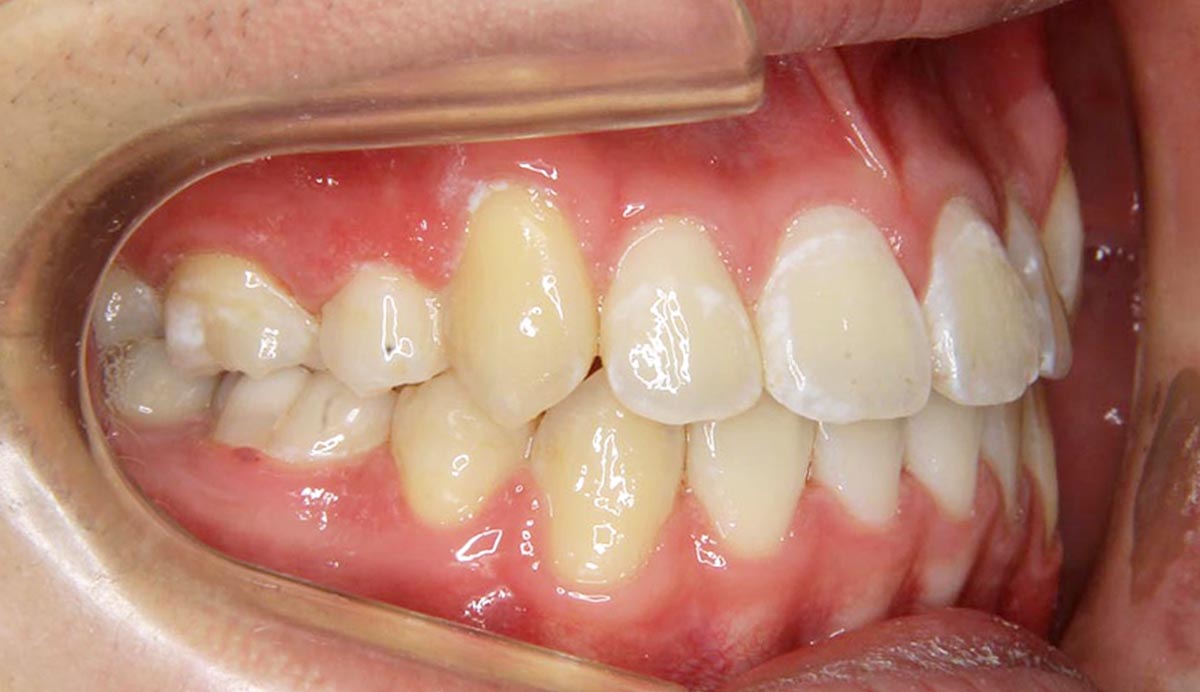

叢生(デコボコ)症例

●主訴

歯のデコボコが気になる

●診断

AngleⅠ級・前歯部叢生

●治療に用いた主な装置

上下顎にマルチブラケット(表側装置)

●抜歯部位

上下左右第一小臼歯4本

●治療期間

2年6ヶ月

●治療費用

約92万円(ともに税込、調整費、保定費まで含む総額制)

●付記

デコボコがきつかったので抜歯症例となりました。

リスクとして、

①歯根吸収…今回は全くありませんでした。

②カリエス(むし歯)…今回は治療途中でむし歯治療を行いました。

③あともどり…保定装置の装着をしっかりしていただいています。